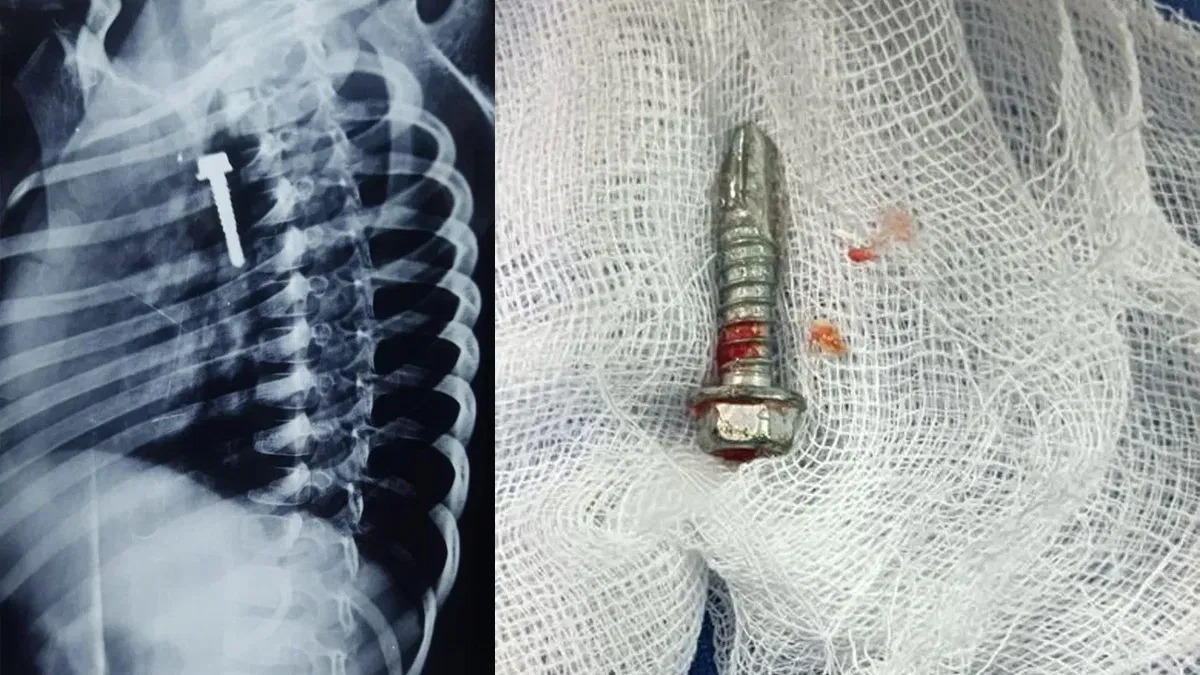

ಖಮ್ಮಮ್ ಜಿಲ್ಲೆಯಲ್ಲಿ ಈ ಘಟನೆ ನಡೆದಿದ್ದು, ಮಕ್ಕಳು ಹಾಗೂ ಪಾಲಕರು ಎಷ್ಟು ಎಚ್ಚರಿಕೆ ವಹಿಸಬೇಕು ಎಂಬುವುದು ಈ ಸುದ್ದಿಯಿಂದ ತಿಳಿದು ಬರಲಿದೆ. ಖಮ್ಮಂ ಜಿಲ್ಲೆಯ ಬದ್ವತ್ ಹರ್ಷ್ ಎಂಬ 6 ವರ್ಷದ ಬಾಲಕ ಆಟವಾಡುತ್ತಿದ್ದ ಸಂದರ್ಭದಲ್ಲಿ ಒಂದು ಇಂಚು ಉದ್ದದ ಬೋಲ್ಟ್ ನುಂಗಿದ್ದಾನೆ. ಇದನ್ನು ಕಂಡ ಪೋಷಕರು ಆತಂಕಗೊಂಡು ಆಸ್ಪತ್ರೆಗೆ ದಾಖಲಿಸಿದ್ದಾರೆ. ವೈದ್ಯರು ಬೋಲ್ಟ್ ಇರುವುದನ್ನು ಪತ್ತೆ ಹಚ್ಚಿ, ಯಾವುದೇ ಶಸ್ತ್ರ ಚಿಕಿತ್ಸೆ ನಡೆಸದೆ ಎಂಡೋಸ್ಕೋಪಿ ಮೂಲಕ ಬೋಲ್ಟ್ ಹೊರ ತೆಗೆದಿದ್ದಾರೆ.

ಈ ಅವಧಿಯಲ್ಲಿ ಇಂತಹ ಘಟನೆಗಳು ಹೆಚ್ಚಾಗಿ ನಡೆಯುತ್ತಿದ್ದು, ಪಾಲಕರು ಎಚ್ಚರಿಕೆಯಿಂದ ಇರಬೇಕು ಎಂದು ವೈದ್ಯರು ಕಿವಿ ಮಾತು ಹೇಳಿದ್ದಾರೆ.